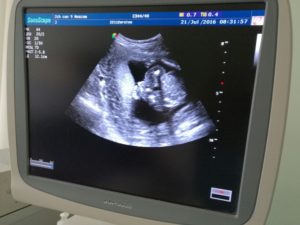

Сначала беременная проходит ультразвуковую диагностику. Процедура полностью безболезненна и безвредна для плода. УЗИ на 2-м скрининге делается для соотношения установленных норм показателей измерения частей тела и органов плода с индивидуальными результатами обследования у беременных.

Врачи в основном смотрят результаты УЗИ на 2-м скрининге. Биохимический анализ крови назначается при особых показаниях, когда у будущей матери выявлены риски на скрининге в первом триместре. В результатах УЗИ 2-го скрининга указывают внешние данные ребенка: размеры всех частей тела, рост, вес, количество плодов в матке.

После анализа внешних данных сонолог переходит к фетометрии, оценке анатомического строения плода при скрининге 2-го триместра. Обследуются кости ребенка, измеряется длина конечностей, определяется состояние внутренних органов и их развитость.